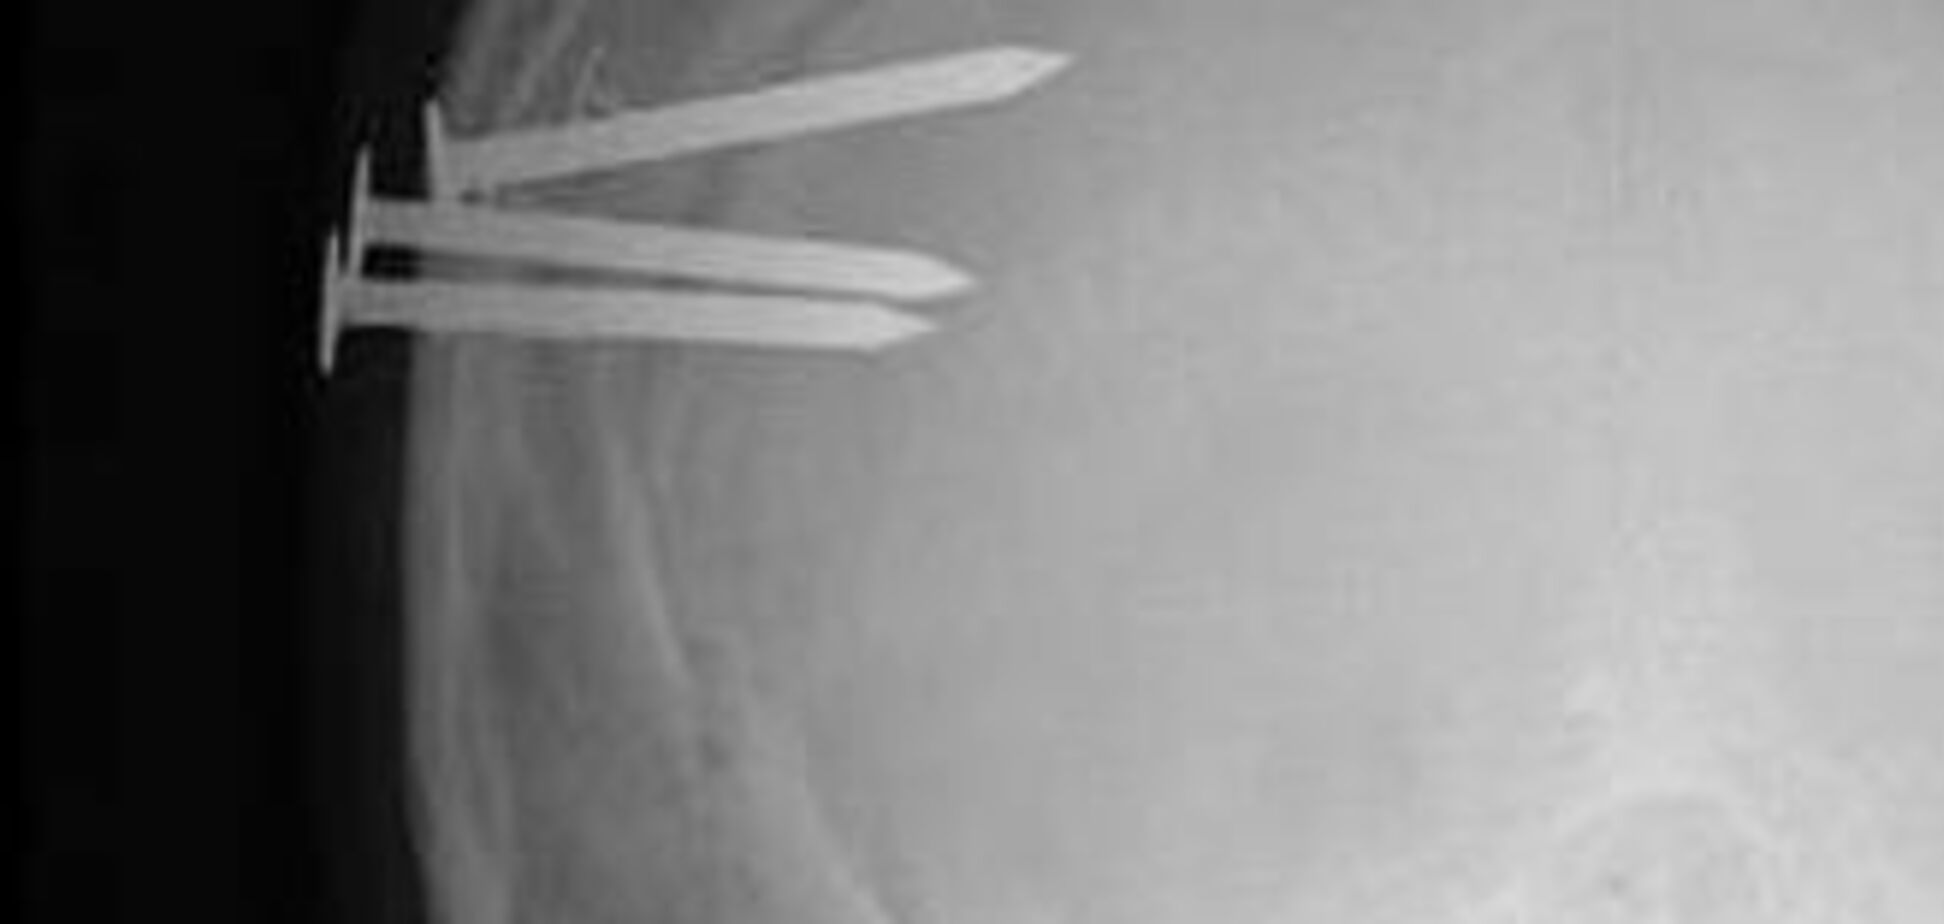

Найдивніші і дивовижні рентгенівські знімки

Якщо зібрати офіційні медичні документи з усього світу, можна дізнатися багато цікавого. Ці рентгенівські знімки, наприклад, є чудовою ілюстрацією разючих можливостей людського тіла і розуму, пишуть АиФ